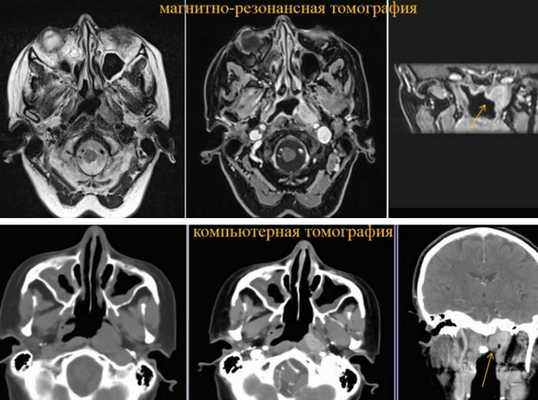

Магнитно-резонансный и компьютерный снимки в оценке опухоли

В онкологической практике врачи рассматривают КТ и МРТ носоглотки, как взаимодополняющие методы визуализации. При оценке патологии на продвинутых стадиях необходимы оба вида диагностики:

- МРТ носоглотки с контрастом покажет точные границы опухоли, проникновение последней в соседние ткани;

- КТ продемонстрирует изменения в твердых структурах, когда новообразование инвазирует в кость, вызывая деструкцию (разрушение) или узурацию - формирование щели с выделением продуктов распада.

При выборе зоны для лучевого воздействия помимо компьютерной томографии обязательно требуются результаты магнитно-резонансного сканирования. Оба исследования в онкологической практике преимущественно выполняют с контрастированием.

Для первичного обследования пациента с подозрением на злокачественное новообразование носоглотки предпочтительнее сделать МРТ, так как дифференциация мягких тканей на снимках (даже без внутривенного усиления гадолинием) значительно выше, чем при компьютерной томографии.